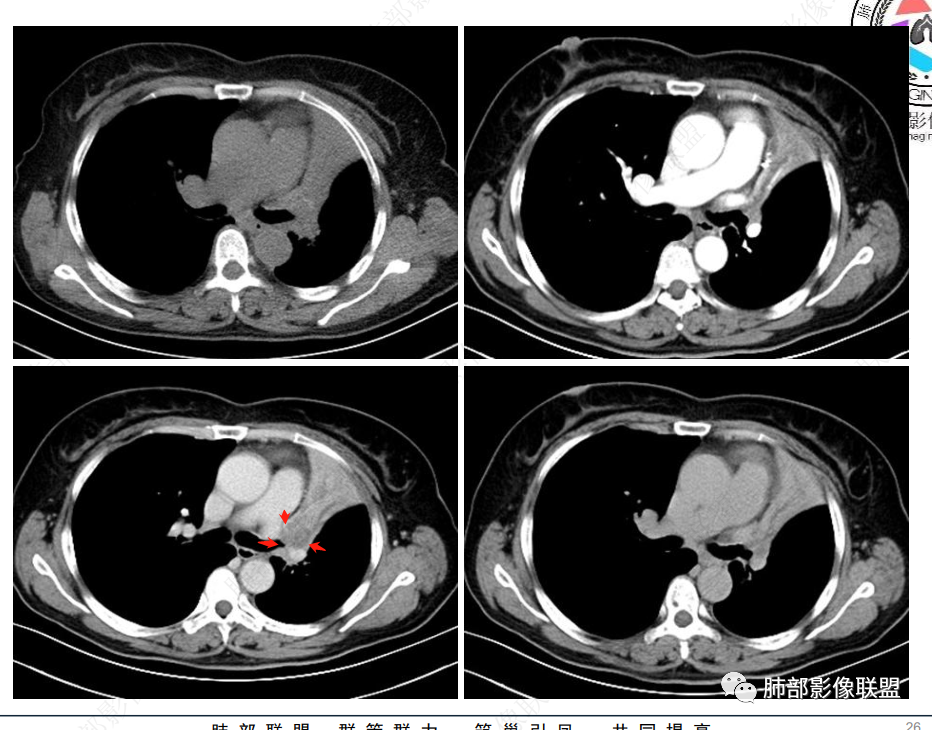

病灶腔内位主,局部膨隆凸向上叶支气管,两侧壁不清,病灶明显突出于壁外。

外形近端膨隆,远端收缩。

局部肺动脉受压明显,受压处似乎有点边界不清。

远端走形自然,提示远端不张,强化最明显处应该是单纯不张肺组织。

近端病灶内强化偏低,提示有侵犯。

综上,腔内占位明确,周围侵犯明确,支持支气管腔内恶性肿瘤,并阻塞性不张。

2、影像表现:正常肺背景,左肺上叶支气管腔内占位,上叶支气管截断,远端肺组织不张,强化差异衬托出肺门区结节影或块状影。增强扫描腔内占位轻中度不均匀强化,可见坏死,远端粘液栓,局部肺动脉受压、侵犯,纵膈淋巴结无明显肿大,无胸腔积液。